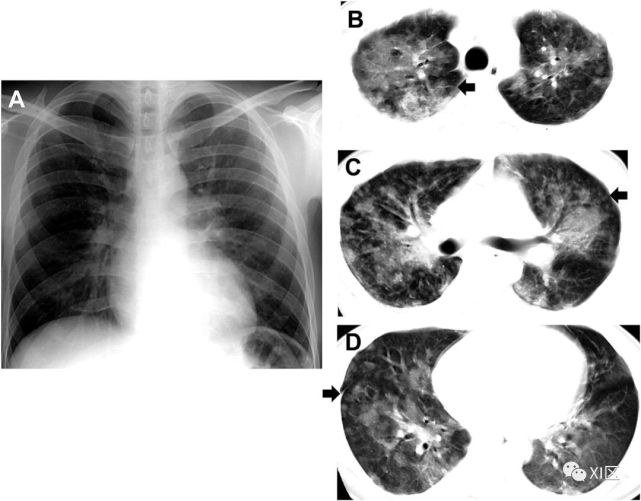

图23 27岁男性,出现咳嗽和咳痰,诊断为MERS冠状病毒引起的肺炎。(上)最初的胸片显示,在下肺的两个区域,特别是在左心后区域,结节影(箭)区域增加。同一天在右下肺静脉水平(中上)以及右心房和下腔静脉交界处(中下)的冠状位重建图像(3mm) 椎体水平的图像(下)显示了两下肺叶的多发斑块状和结节样实变和GGO(箭头)。